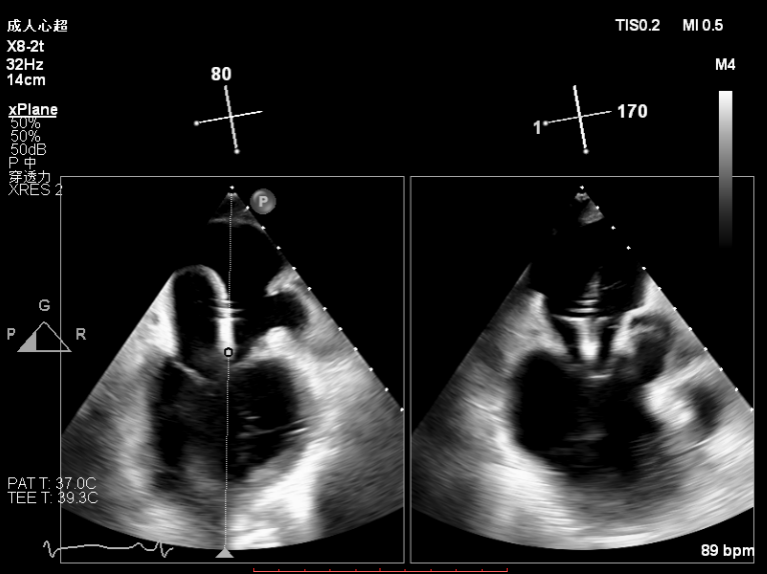

2.X-plane切面调整瓣膜夹的位置:主要定位PISIA最明显的A2/P2区,分别二尖瓣交界联合切面和 LVOT切面调整夹子轴向,同时在3D切面上观察夹子方位和区域,瓣膜夹位置良好,轴向和方位均理想后,捕获A2/P2偏1区处的前后瓣叶,逐渐关闭瓣膜夹,TEE显示二尖瓣反流明显减轻至微量,3D视角显示组织桥连续完整,瓣叶抓捕稳定。彩色血流提示微量的瓣膜反流,测量平均跨瓣压差3mmHg,复查左上肺静脉血流频谱恢复正向,手术效果理想,逐步释放瓣膜夹系统撤出体外。